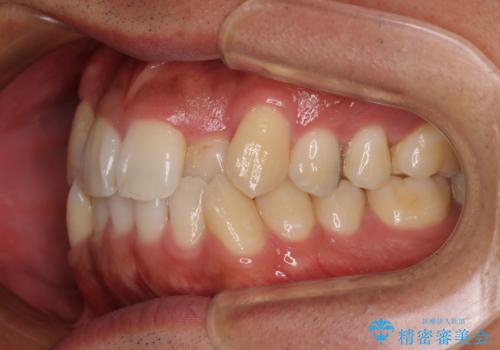

- 「八重歯を治したい」とご相談いただいた患者様の症例をご紹介します。

上下の前歯部に強い叢生(ガタガタの歯並び)があり、そのまま歯を並べると出っ歯になってしまう可能性がありました。

そこで、上下左右の第一小臼歯を抜歯し、歯が並ぶためのスペースを確保し叢生を解消する治療計画を立てました。